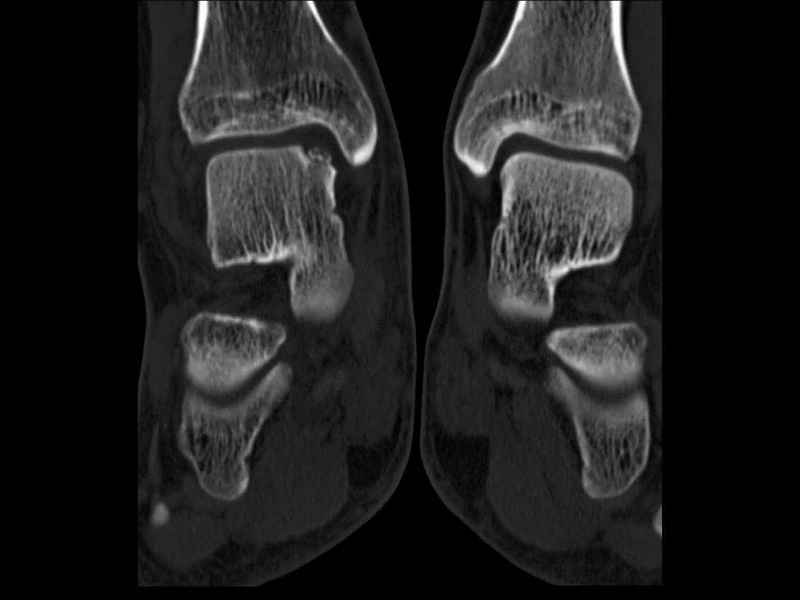

[Ortho] Рассекающий остеходрит + киста шейки тарана

Уважаемые коллеги, обратился за помощью пациент, мужчина, 25 лет. С жалобами на болевой

синдром в области голеностопного сустава и среднем отделе стопы. Травму отрицает. Со слов,

болевой синдром в течении 1 года. Последние 1-1.5 мес периодически вынужден пользоваться

костылями. После ограничения нагрузки боли уменьшаются. Соматически здоров. До появления

болей активно занимался рукопашным боем.

На СКТ картина рассекающего остеохондрита блока

таранной кости, киста шейки таранной кости с признаками импрессии суставной поверхности. А

также - разрастания переднего края б\берцовой кости сопровождающиеся клиникой импиджмент

синдрома.